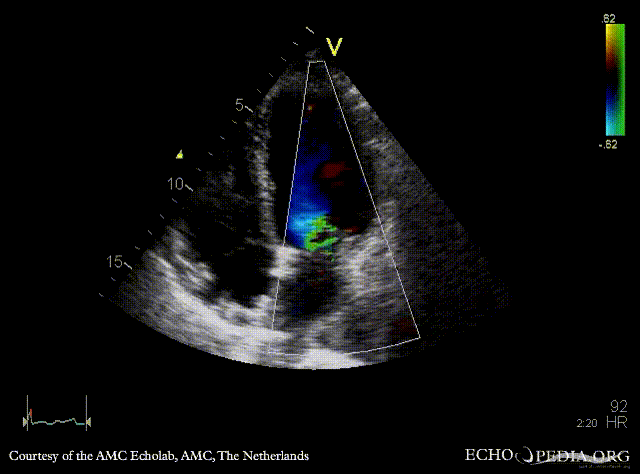

| PSAX: mobile fragment of papillary muscle | A5CH |

| A2CH | A4CH: severe mitral regurgitation, excentric jet |